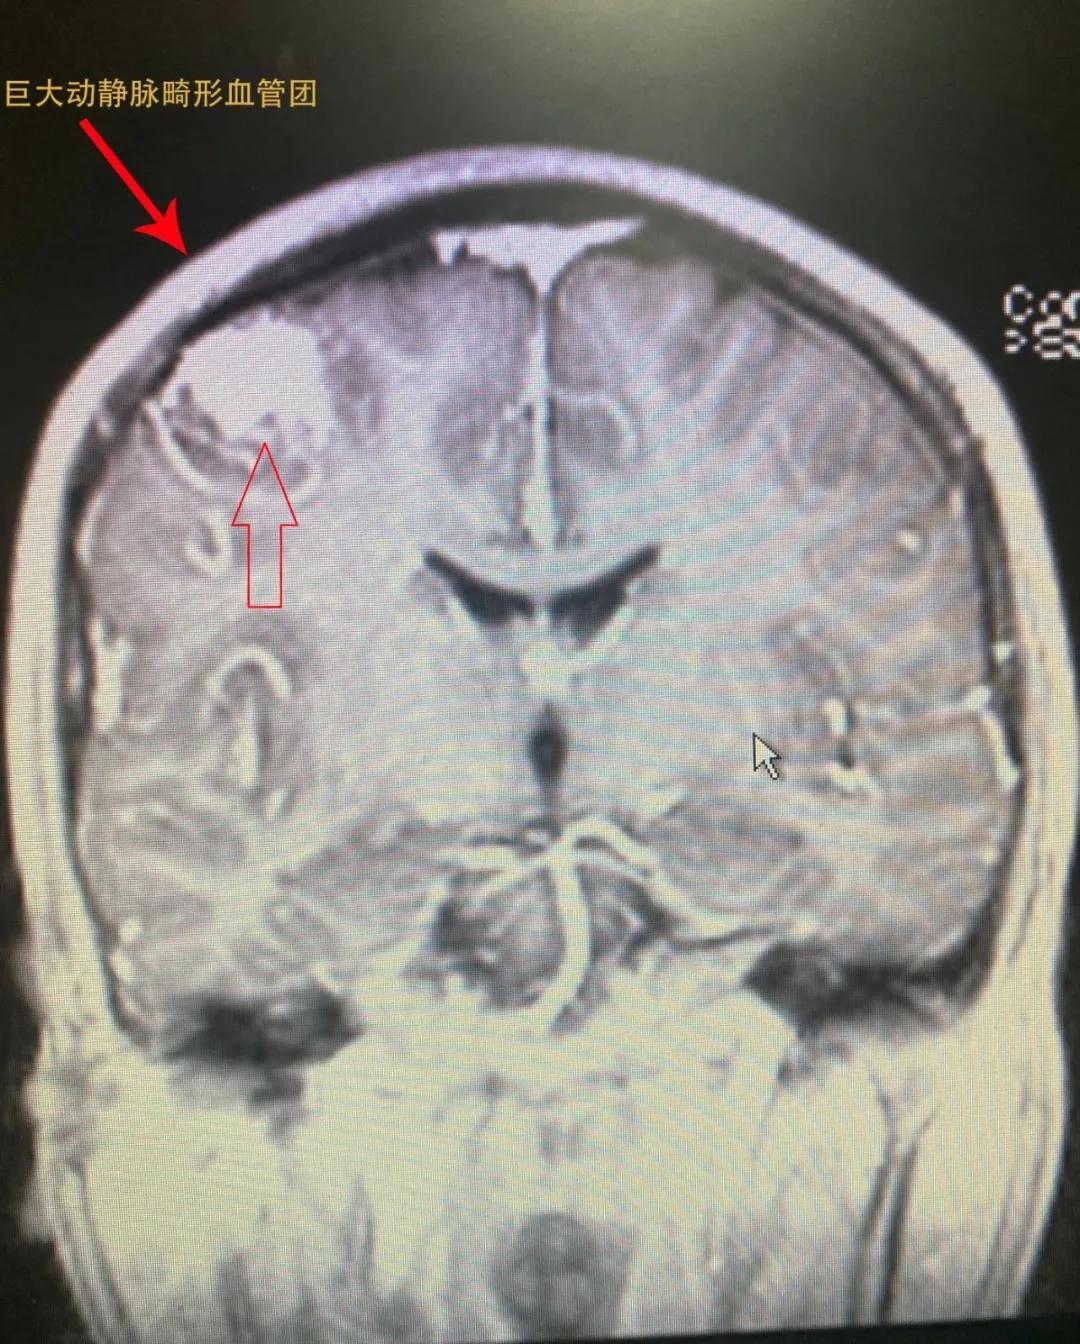

检查结果显示,患者右侧顶部动静脉畸形(供血为大脑中动脉远段分支血管,引流静脉为上矢状窦皮层浅静脉),进一步进行脑血管造影检查——患者右顶叶中央前回功能区动静脉畸形血管团。

术前检查片子